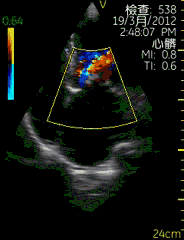

| 图像名称: | 心尖四腔切面(彩色) |

| 心尖四腔切面(彩色) | | 介绍重点: | 房室瓣彩色多普勒显示有心房到心室的单向红色血流 |

| 房室瓣口彩色多普勒显示收缩期有心室到心房的反向蓝色血流 | | 临床用途: | 瓣膜功能正常 |

| 二尖瓣关闭不全,三尖瓣关闭不全 |